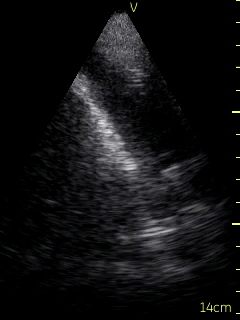

The patient’s right pleural space was assessed by the consultant Respirologist using a VScan device. A small amount of fluid in the right pleural space was noted to be gelatinous in appearance and loculated. Adjustment of the probe to the 6th intercostal space, roughly 10 cm from the spine helped to localize the largest fluid loculation in order to conduct the diagnostic thoracentesis (Figure 3, Video 3).  Following informed written consent, and lidocaine anesthesia in a sterile fashion, an angiocather was introduced guided by the ultrasound location of the largest pocket of fluid.  Approximately 70 ml of bloody fluid was collected.  The patient tolerated the procedure well without complication. Ultrasound post procedure persistence of fluid with several loculations remaining. The collected fluid was sent for routine analysis, cytology, flow cytometry, and culture.